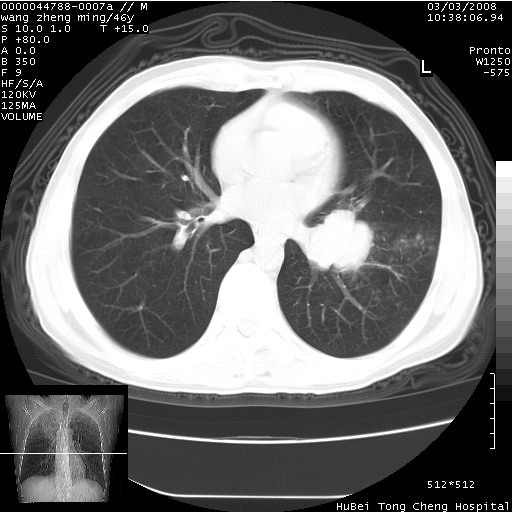

以下是引用卜一在2008-3-22 1:37:00的发言:[br]右肺实质性肿块,边缘不整,明显见毛刺征 分叶征及胸膜凹陷征,右上叶支气管明显变窄,远端散在的片状 斑片状实变影。另:左肺门较大肿块,支气管受累 变窄,远侧见阻塞性肺炎。纵隔内见肿大淋巴结。多考虑:右肺周围性肺癌伴左肺门 纵隔淋巴结转移!